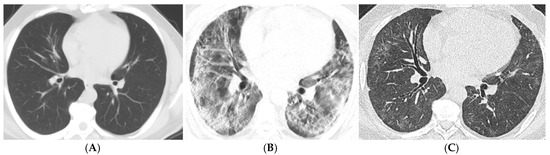

| Imaging Findings (6–12 Months) | Common Findings | Parenchymal bands, traction bronchiectasis |